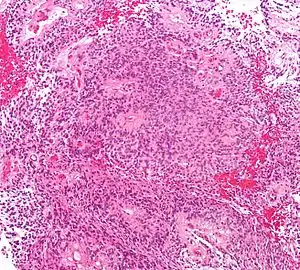

| Micrograph of an ependymoma. H&E stain. | |

Ependymomas are composed of cells with regular, round to oval nuclei. There is a variably dense fibrillary background. Tumor cells may form gland-like round or elongated structures that resemble the embryologic ependymal canal, with long, delicate processes extending into the lumen; more frequently present are perivascular pseudorosettes in which tumor cells are arranged around vessels with an intervening zone consisting of thin ependymal processes directed toward the wall of the vessel.[2]